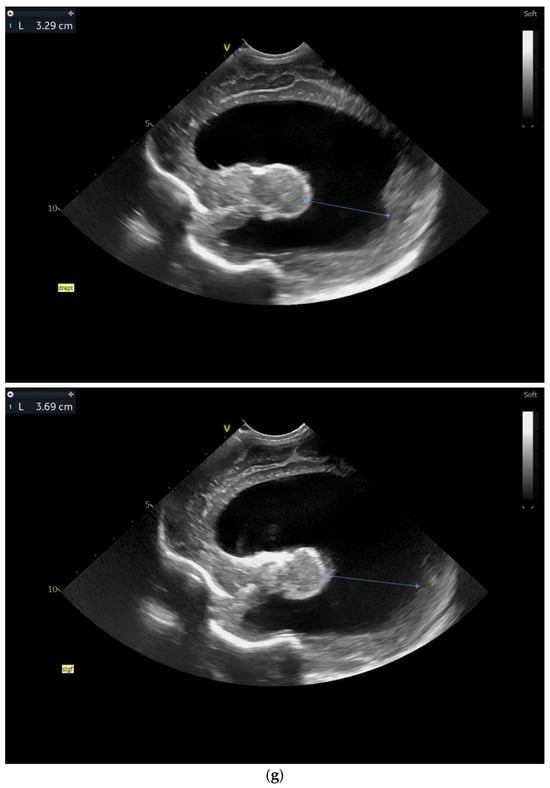

(a) Cranial ultrasound. Coronal view. Lateral ventricles and third ventricle enlargement. L1, L2—Levine index measurement. L3, L4—posterior horn of the lateral ventricles’ width measurement. L5—third ventricle width measurement (personal image collection). (b) Cranial ultrasound. Sagittal view. Enlarged third and fourth ventricles. L1, L2—third ventricle measurements. L3, L4—fourth ventricle measurements (personal image collection). (c) Cranial ultrasound. Sagittal view. Enlarged lateral ventricles. Up—left ventricle. Down—right ventricle (personal image collection). (d) Cranial ultrasound. Coronal view. Punctuate hyperechoic images were observed in the right lobe (personal image collection). (e). Up left—MRI T1 sequence. Up right—MRI T2 sequence—susceptibility weight imaging (SWI). Down—CT scan. Transversal view. Yellow arrows—multiple calcifications can be seen in the CT scan (personal image collection). (f) Cranial ultrasound. Coronal view. Lateral ventricles. L1, L2—Levine index measurement. L3, L4—anterior horn width measurement. Blue arrow—intraventricular shunt (personal image collection). (g) Cranial ultrasound. Sagittal view. Thalamo-occipital distance measurements. Up—right ventricle. Down—left ventricle (personal image collection).

At six weeks after birth, an MRI scan was performed, while a CT scan was performed at 14 weeks of life, both providing valuable information regarding the sequelae of Toxoplasmosis (Figure 4e). Even though a few signs were observed on the MRI, the CT scan better outlined the presence of the parenchymal calcifications. A neurosurgical intervention was intended, a ventricle puncture was performed, and a shunt was placed in the right ventricle. The cranial ultrasound at two months of life did not show notable improvements, however (Figure 4f,g). The neurological examinations showed axial hypotonia and limb hypertonia.